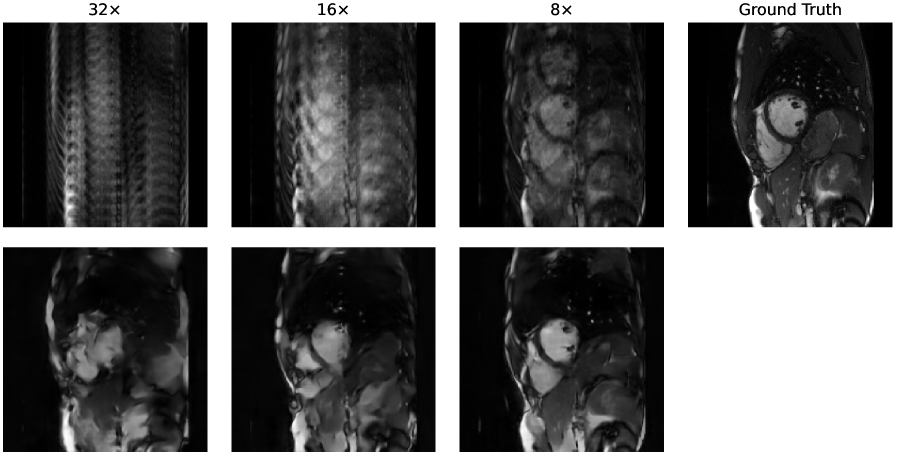

4.1 Reconstruction and Segmentation Performance

To validate the underlying models, we evaluated reconstruction quality using the Structural Similarity Index (SSIM) and Peak Signal-to-Noise Ratio (PSNR), and segmentation accuracy using the Dice Similarity Coefficient (DSC). For the DSC computation, we first calculated the average DSC score across all segmented structures for each patient, and then averaged these scores across all patients. Figure 2 shows that for both datasets, all metrics improved as the acceleration rate decreased, with the highest scores achieved in the fully-sampled setting. This trend is expected, as more k-space data provides more information for both reconstruction and the downstream segmentation task.

We also observed that performance on the CINE dataset was notably lower than on the SKM-TEA dataset across all acceleration factors. This difference can be attributed to the more challenging VISTA undersampling pattern used for the CINE data, which tends to produce stronger aliasing artifacts in zero-filled images compared to the Poisson-disk sampling used for SKM-TEA.

4.3 Qualitative Results

To provide a qualitative understanding of our dynamic stopping mechanism, Figures 4 and 5 show representative cases of both early and late scan terminations. Each figure visualizes the evolution of the reconstruction, segmentation, and the downstream metric along with its calibrated uncertainty as more k-space data is acquired. As expected, we observe a consistent trend across all examples: as the acquisition progresses, reconstruction quality and segmentation accuracy visibly improve. Moreover, the prediction uncertainty decreases the more k-space data is being collected. Additional reconstruction examples are displayed in Figure 6 and 7. Concurrently, the downstream metric estimation converges toward the ground truth value while the corresponding uncertainty bands narrow. Crucially, instances of high uncertainty consistently correspond to visible artifacts, segmentation errors, and larger deviations in the final metric, confirming that our uncertainty estimates effectively track acquisition quality.